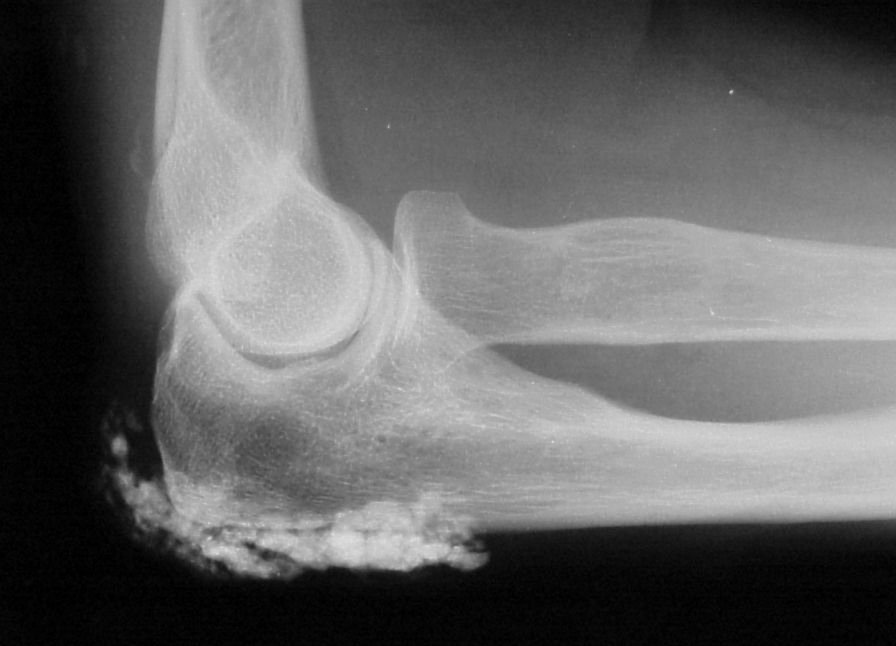

Subcutaneous calcification of the extensor surface of the elbow is common, and a common site for spontaneous drainage and infection.